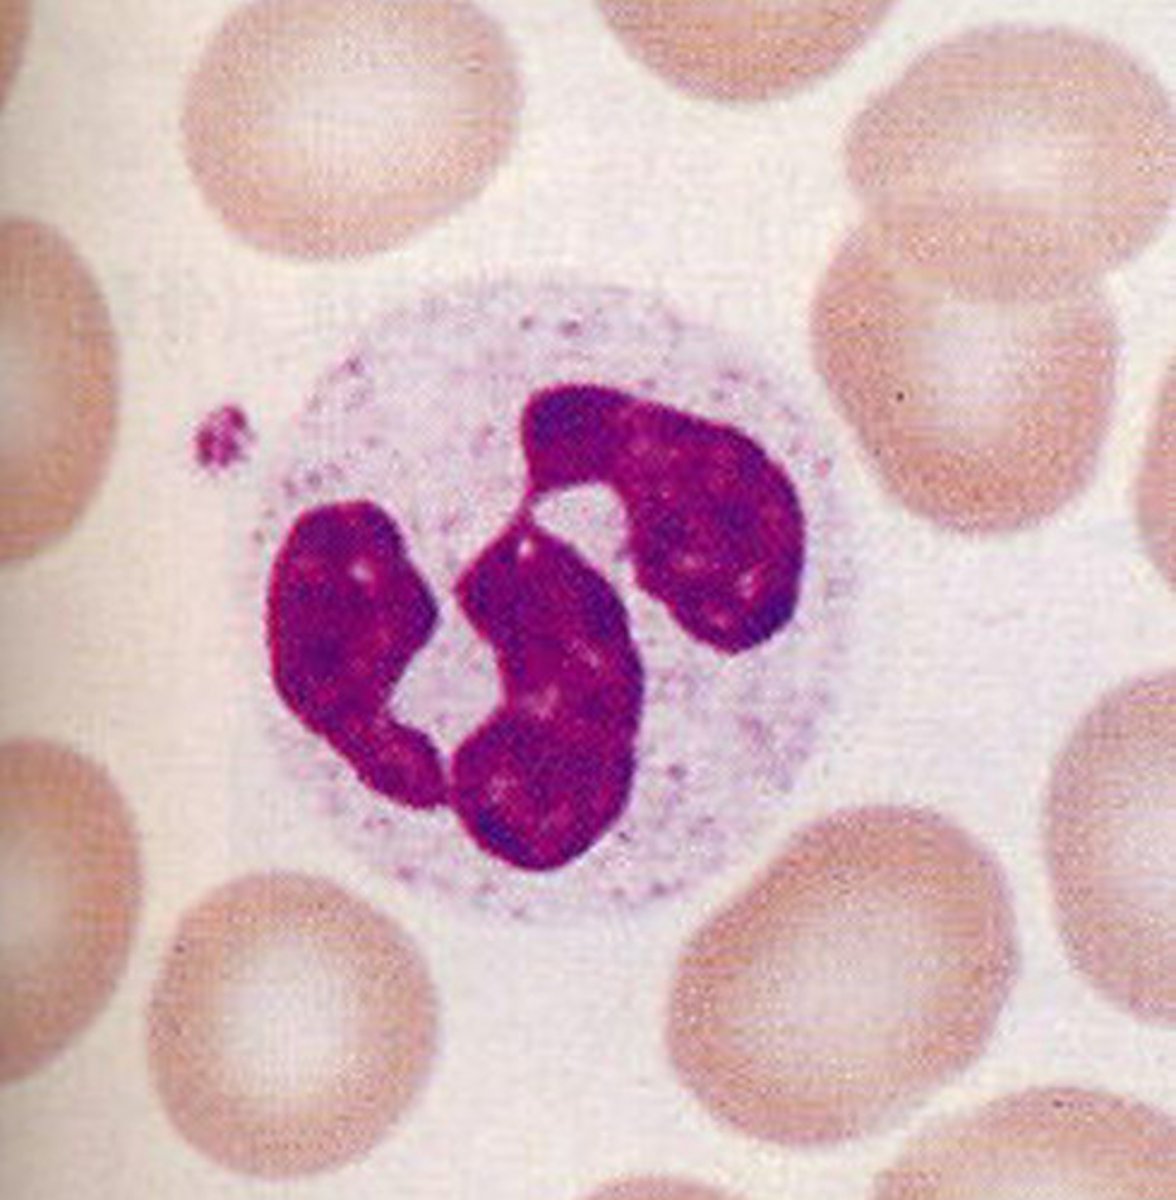

Monocytes

Structure: Largest WBCs, U shaped nucleus

Function: A large WBC that transform into macrophages to fight off viruses and chronic infections